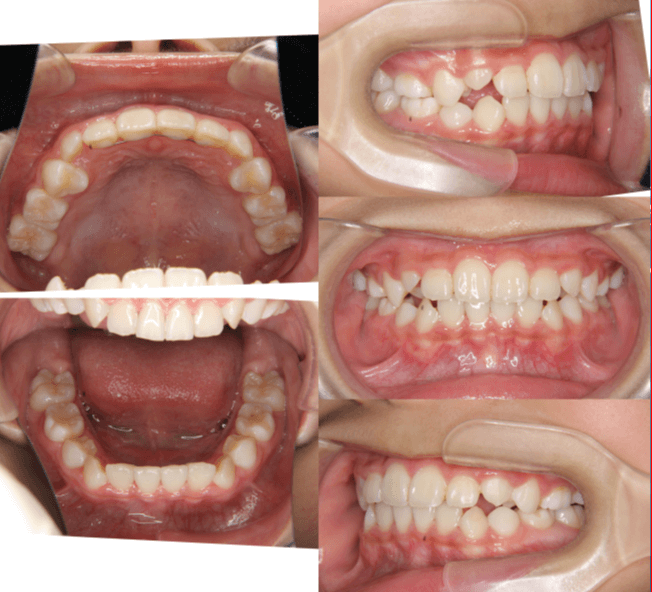

| 年齢・性別 | 11歳1ヶ月の女性 |

|---|---|

| 主訴 | 口元の突出感と歯並びが気になり、将来的な咬合状態を整える目的で来院された患者様です。 |

| 治療期間・回数 | 2年6ヶ月・25回 |

| 費用 | 720,000円 |